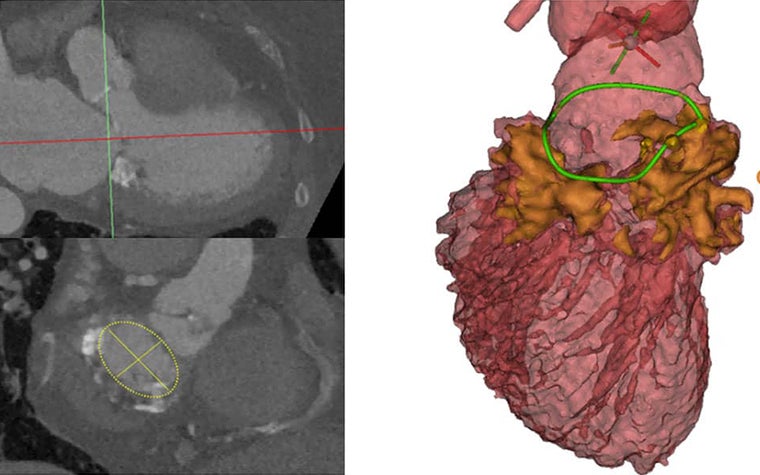

Initially, when they reviewed the CT scans using their 2D planner evaluation methods, they measured the annulus on the 2D slice that visualized it best. Based on their measurements, they believed a 29 mm implant would work for the patient. After uploading the data into Mimics Enlight, they were able to visualize the entire calcification zone, in 3D.

“If you switch around different views, you can get a great image of how the calcium is distributed. Not only the X and the Y planes — but, also in the Z plane, the third dimension. And, by doing measurements in those three planes, we can obtain another kind of measurement of the annulus,” explained Dr. Ooms.

Based on the more detailed visual of where the calcium was and their new measurements, they were able to determine that in fact, a 26 mm valve would be more suitable for the patient. This meant that the valve implant would safely stay in the location that it was implanted. More importantly, the implant would not cause an acute obstruction of the left ventricular outflow tract (LVOT) which means that enough blood can’t flow to the body, including the brain. Obstruction of the LVOT has deadly consequences without emergency surgery.

“I think what is crucial is that the anatomical appreciation was different with conventional CT and with 3D planning. We added so much more granularity to our understanding using the 3D planning. And that resulted in a safer approach with less risk of significant complications like obstructing the LVOT due to a neo-LVOT that would have been too small for the patient. Based on the calcium distribution and the 3D appreciation, we realized that a 26 mm would already anchor properly in this case," explained Prof. Van Mieghem.